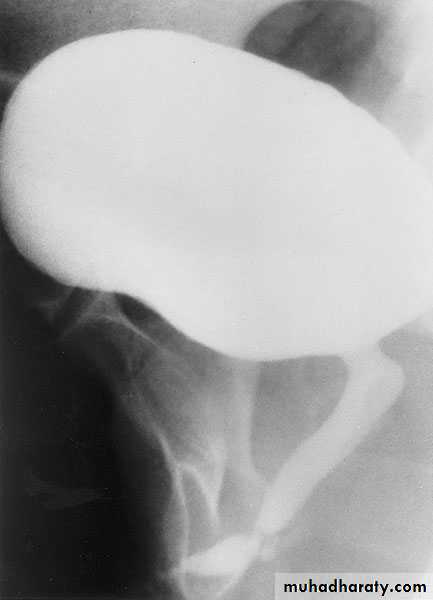

CYSTOURETHROGRAPHY

Contrast-enhanced imaging of the lower urinary tract provides valuable information on the function and anatomy of the bladder and urethraVoiding ( micturating) Cystourethrography (MCUG): looking for vesicoreteric reflux